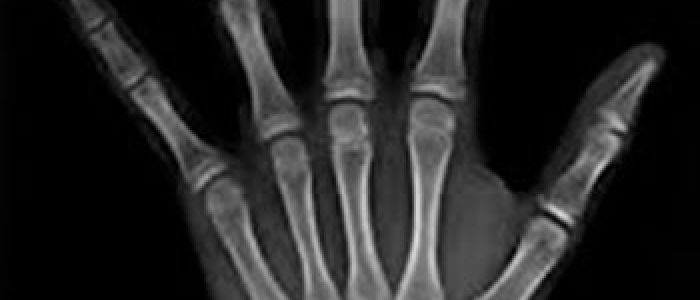

Las radiografías extraorales se emplean cuando no es factible obtener información diagnóstica adecuada en las series de radiografías intraorales, es así que son utilizadas para observar un área grande de los maxilares y del cráneo en una sola radiografía. Los exámenes radiográficos extrabucales tienen el propósito de evaluar áreas grandes del cráneo, dientes impactados y patrones de erupción, crecimiento y desarrollo; examinar la extensión de lesiones grandes, traumatismos, articulación temporomandibular. Son de mucha utilidad principalmente en Ortodoncia y Cirugía Bucal.

Existen varias radiografías extraorales entre las cuales se tiene: